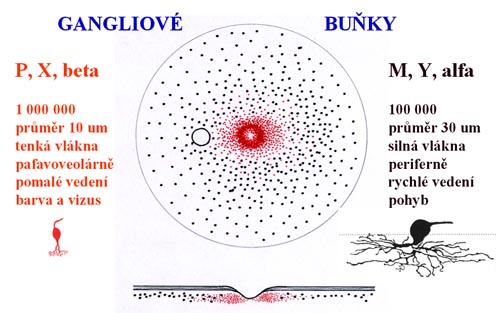

Gangliové buňky

V 5. týdnu embryonálního života vzniká primitivní terč zrakového nervu a začínají se vytvářet první buňky budoucí sítnice - gangliové buňky a Mullerovy buňky.

Buňky v centrální části sítnice se začínají diferencovat nejdříve a již za týden jejich výběžky dosahují až k terči. Tak vzniká základ makulopapilárního svazku. Během dalších několika dnů se diferencují gangliové buňky v perifernějších oblastech sítnice. Těm, které rostou z temporální strany, překáží v cestě ke zrakovému nervu již vytvořený makulopapilární svazek a musí jej obloukovitě obejít. Vlákna rostoucí z gangliových buněk z nasální strany takovou překážku na cestě nemají a jejich průběh ke zrakovému je přímý. Tímto způsobem během několika dní vzniká vrstva nervových vláken. Její uspořádání nám umožňuje pochopit lokalizaci skotomů zorného pole.

Je tvořena axony gangliových buněk pokrytých astrocyty, probíhajících v kanálcích z výběžků Mullerových buněk ve svazečcích o průměru 20 um. Svazečky jsou morfologickým podkladem jemného žíhání. Světlé proužky mezi tmavými mezerami jsou výběžky Mullerových buněk, ve kterých probíhají nervová vlákna. Temporálně i nasálně je žíhání jemné a každý proužek je tvořen jedním svazečkem vláken. V horním i dolním temporálním kvadrantu je jsou proužky silnější a tím i lépe viditelné, každý proužek má několik svazečků (svazečky jsou v několika vrstvách).

Při progresi glaukomu nejprve bývají poškozeny gangliové buňky v blízkosti temporálního švu sítnice. Jejich axony probíhají v hlubší vrstvě nervových vláken a do zrakového nervu pronikají v jeho periferii. Protože vzniklý defekt je překryt dalšími povrchnějšími vrstvami, výpadek není při pozorování sítnice zřetelný. Až po ztrátě poloviny vrstvy nervových vláken se defekt stává zřetelným oftalmoskopicky.